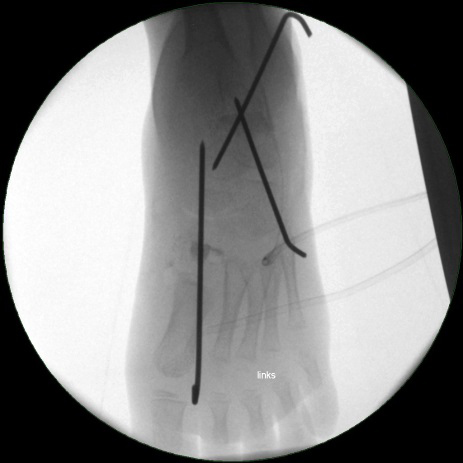

• Stabilisierung des Spanes mit Kirschnerdrähten (Bild 18).

• Röntgenkontrolle (Bild 21,22).